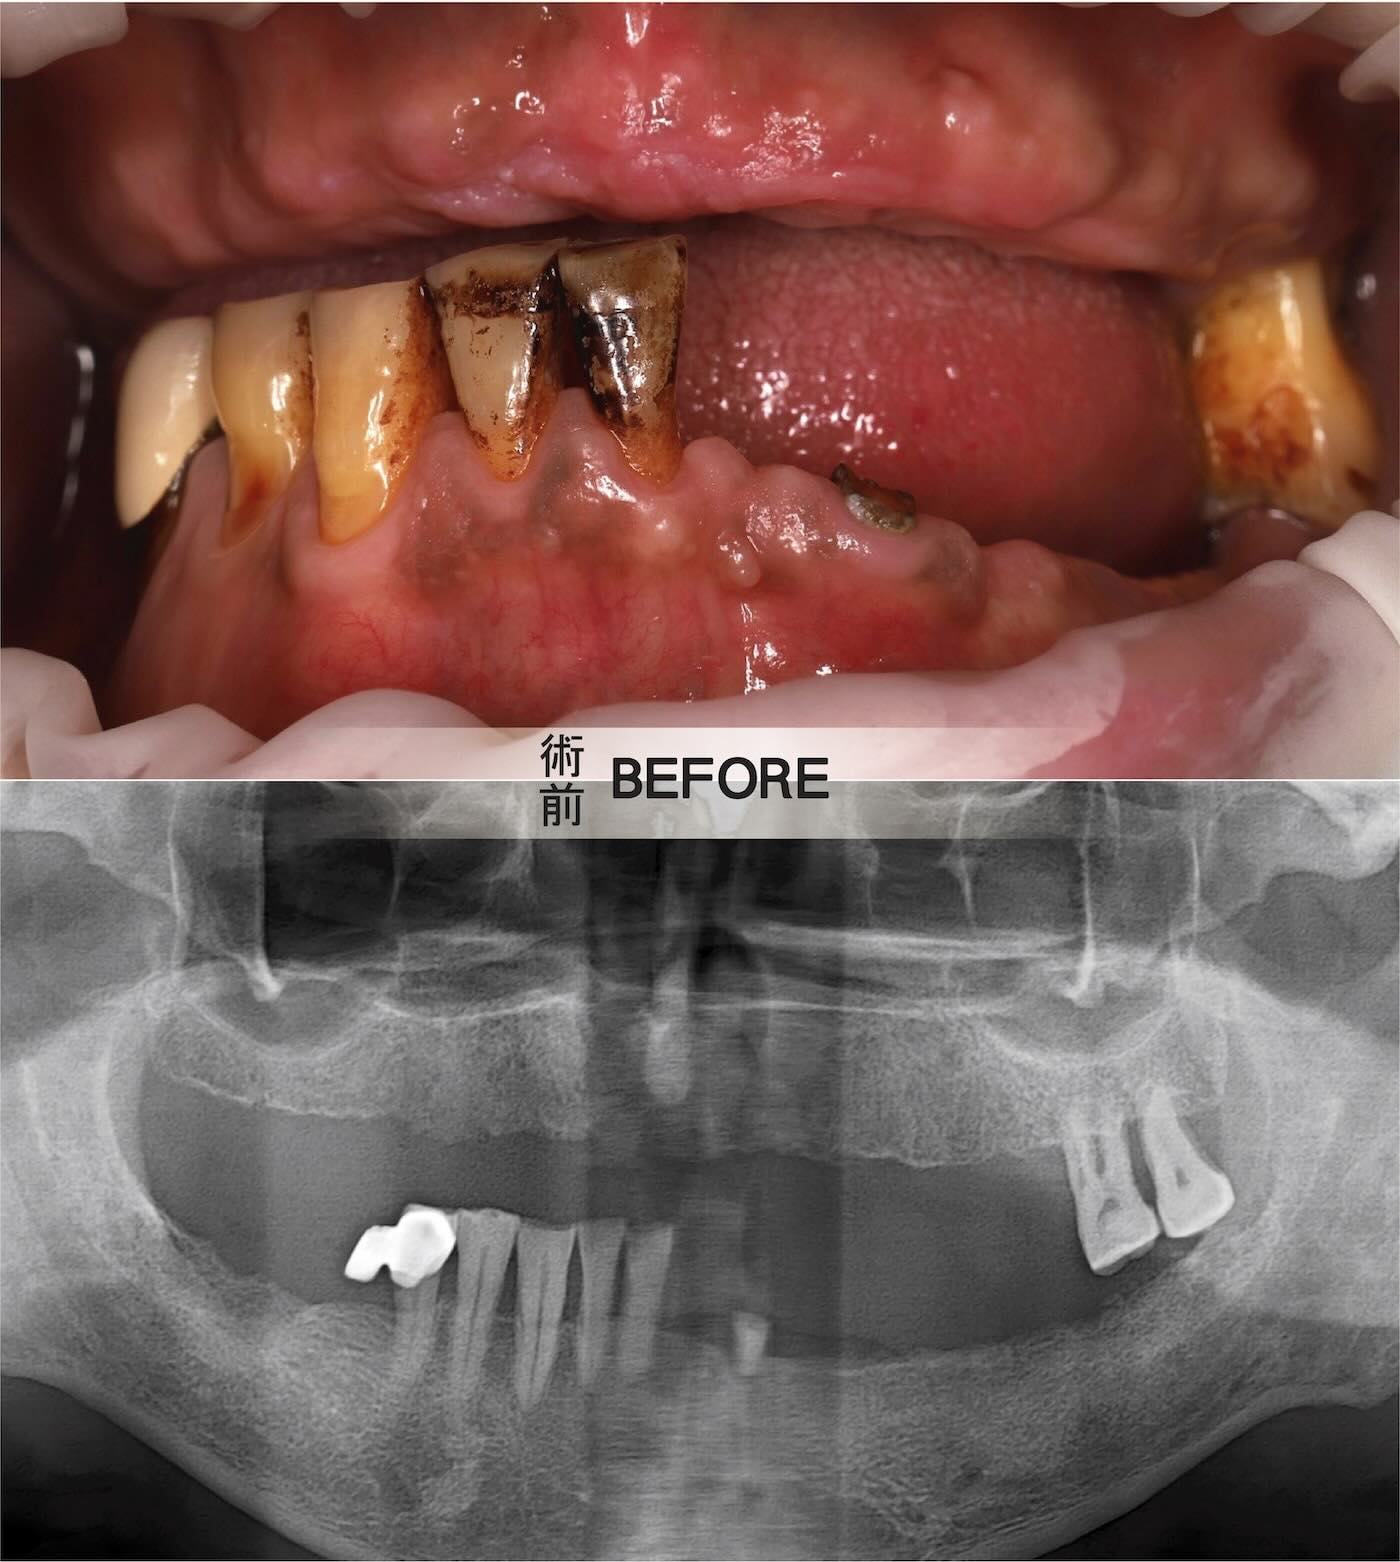

許多長期配戴活動假牙或是缺牙的患者,生活中總伴隨著咬合不穩與異物感的困擾。患者吳先生坦言,他早已受夠了吃飯時需時時遷就假牙、不敢大口咀嚼的日子。

然而,重建之路並不容易。吳先生因長期服用抗凝血劑且腎功能不佳,曾諮詢多家診所皆因手術風險讓他望而卻步。

對於高血壓或是長期服用抗凝血劑 (Anticoagulants) 的患者而言,傳統翻瓣手術傷口範圍較大,容易增加術中出血與術後腫脹風險,因此,御耀團隊在精密評估後,為吳先生量身規劃「數位導航微創 All-on-6 全口重建」治療計畫。